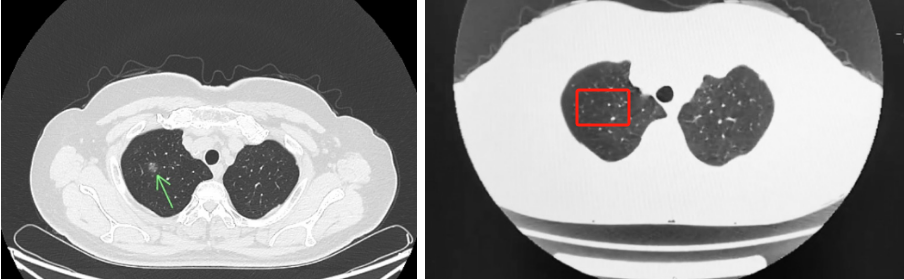

几副汤药,化解开胸之忧!——湖北省第三人民医院中医科运用中医药逆转1.1厘米肺结节